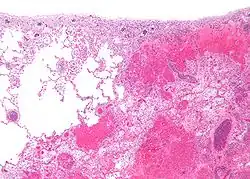

Grossolanamente si può distinguere tra "infarto bianco", ovvero di natura puramente ischemica, e "infarto rosso", cioè seguito da stravaso di sangue conseguente alla necrosi dei vasi sanguigni della zona interessata.